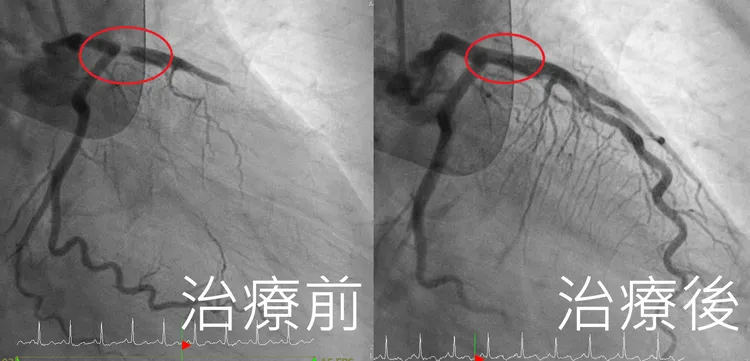

由於患者血壓仍不穩定,為穩定血液循環,心臟外科黃俊晟醫師緊急裝置葉克膜維生,之後再轉入心導管室,由王宇澄醫師執行導管檢查,赫然發現患者左前降支冠狀動脈阻塞高達99%,「有如公路斷崖」,屬於極為致命的血管病變,評估後迅速施行冠狀動脈支架置入術,順利打通血管,恢復血流通暢,2小時內成功續命,過程可說是驚心動魄。

患者左前降支冠狀動脈阻塞高達99%(左),醫師形容「有如公路斷崖」。亞大附醫提供